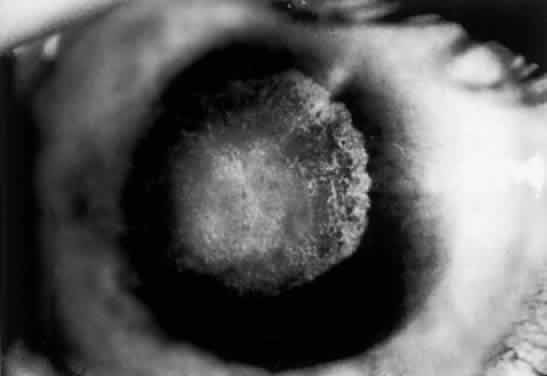

OCULAR FINDINGS. The outstanding clinical feature common to all three phenotypes is the corneal and conjunctival cystine crystal deposition (Figs. 3 and 4). Photophobia is often the only presenting visual symptom; this may be incapacitating and associated with blepharospasm.

Fig. 4. Cystinosis. Top, Transmission electron micrograph showing a stromal keratocyte containing a number of needle-shaped crystalline profiles limited by unit membranes. (× 19,000.) Bottom, Electron micrograph of conjunctival fibrocyte revealing crystalline profiles of sparse granular material within membrane-limited lysosomes. (× 30,000.) (Courtesy of Dr. Kenneth Kenyon)

Corneal deposits appear as a layer of homogeneously distributed, fusiform or needle-shaped, iridescent crystals situated in the stroma beneath the epithelium. In the infantile form, anterior crystal deposition begins early in life (between 6 and 15 months of age) and proceeds posteriorly as the patient ages; deposition advances more rapidly in the periphery. The anterior location of the crystals may be associated with recurrent erosions.33 The depth of the stromal deposition and the density of crystals is always greater peripherally than centrally. More and larger crystals occur in the superficial stroma. No visual impairment occurs at this early stage. By the age of 7 years, most patients have crystals, either within or on the endothelial surface34,35; markedly decreased corneal sensitivity is also present.36 The spherical contrast sensitivity function is significantly lower in infantile cystinosis than in age-matched controls.37